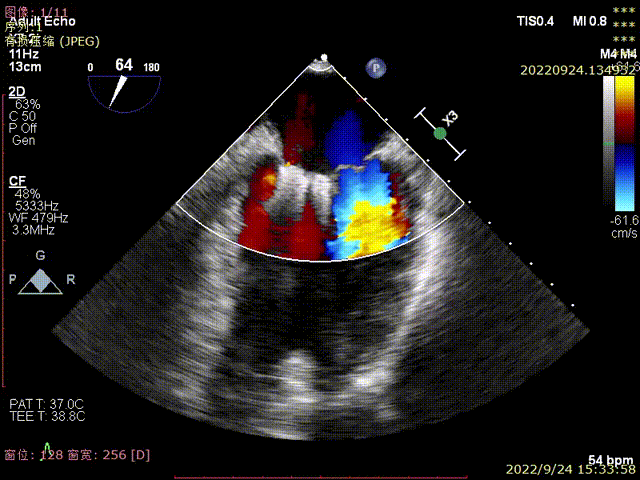

图1-2,术前心超显示大量偏心性二尖瓣反流(反流位置位于P3近PC位置)

图3,由于患者反流位置位于3区偏交界,在MultiVue模式指导下进行操作